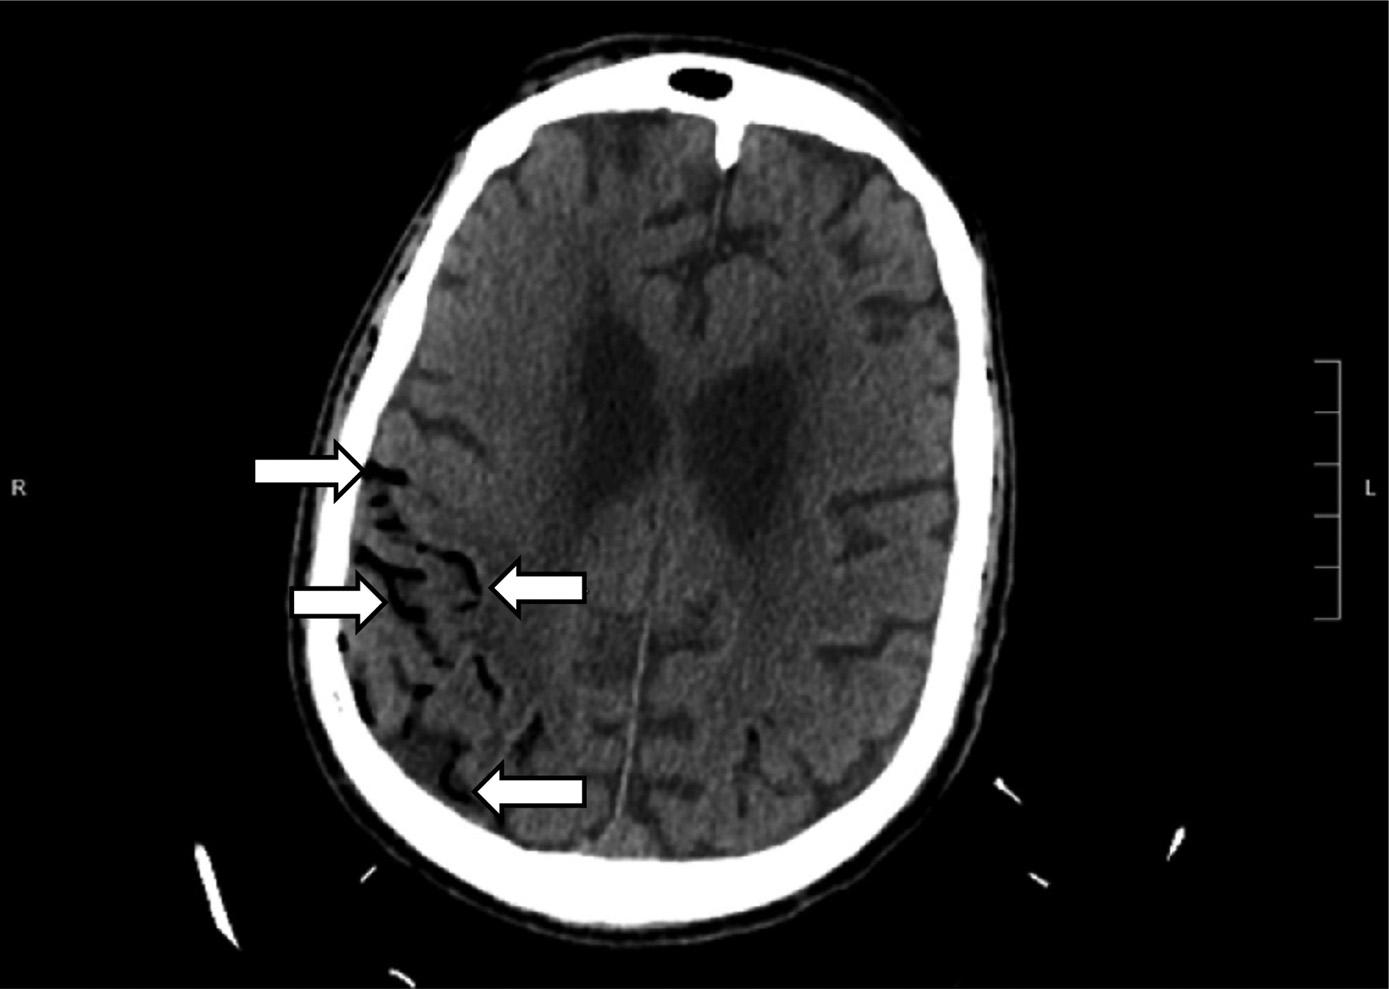

ThepatientunderwentanemergentCTofthehead (Image3)duetothechangeinmentalstatus.Theradiology impressionoftheCTrevealed “extensivevenousgas,which

Computedtomographyofthebrainofa77-year-oldman afterarapidchangeinmentalstatusshowingextensivevenous gas(whitearrows)intherightparieto-occipitalregion.

mayindicategasemboluswithpossibleevolvinginfarctionin therightparietalregion.Nohemorrhageorshift.Further evaluationwithmagneticresonanceimaging[MRI]maybe useful.Largegoiter.” Immediatelytheteamassessedthe patient’scentralvenouscatheterandfoundanuncappedline. Aftertheairwaswithdrawnfromtheline,thelinewas capped.Thepatientwastransferredtotheintensivecareunit atourhospitalforfurthermanagementandahyperbaric medicineconsultation.Heunderwentahyperbaricoxygen therapytreatmentwithresolutionofthegasontherepeatCT head.Afollow-upMRIrevealedmultifocalinfarctsin multiplevascularterritories.